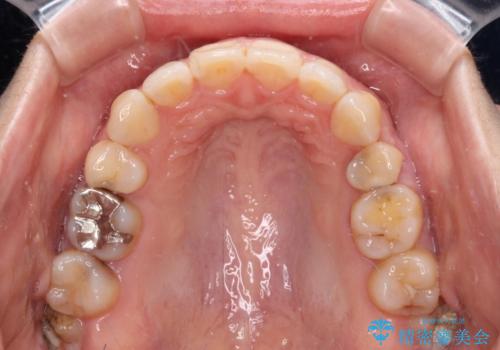

- 口元の閉じにくさと、前歯のでこぼこの歯並びを気にして来院された患者様です。

口元を積極的に引っ込めるために、上下左右の小臼歯計4本を抜歯することとしました。

セオリーでは第一小臼歯を抜歯しますが、上下右側は第二小臼歯に銀歯が装着されているため、第二小臼歯を抜歯することとしました。